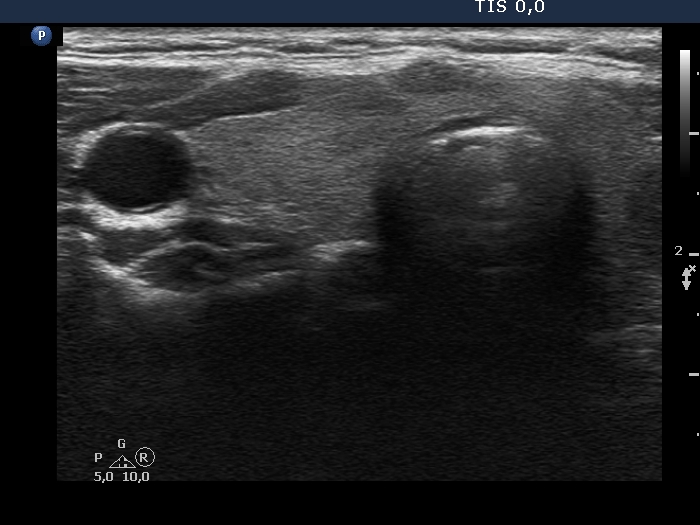

First examination (first row of images):

Clinical presentation: A 39-year-old woman was referred for evaluation of a nodule detected on ultrasound screening. Cytology resulted in benign lesion. The aTPO level proved to be elevated.

Palpation: a firm lesion in the left lobe.

Functional state: euthyroidism (TSH 2.65 mIU/L, anti-TPO > 1300 U/mL).

Ultrasonography. The thyroid was echonormal and has several small, moderately hypoechoic areas corresponding to thyroiditis. There was a hypoechoic nodule in the left lobe. The lesion had microcalcifications, presented with irregular, lobulated margins and showed a combined perinodular and intranodular vascularity.

Considering the ultrasound presentation, we performed cytology which resulted in non-diagnostic result.

Suggestion: ultrasound in a year.